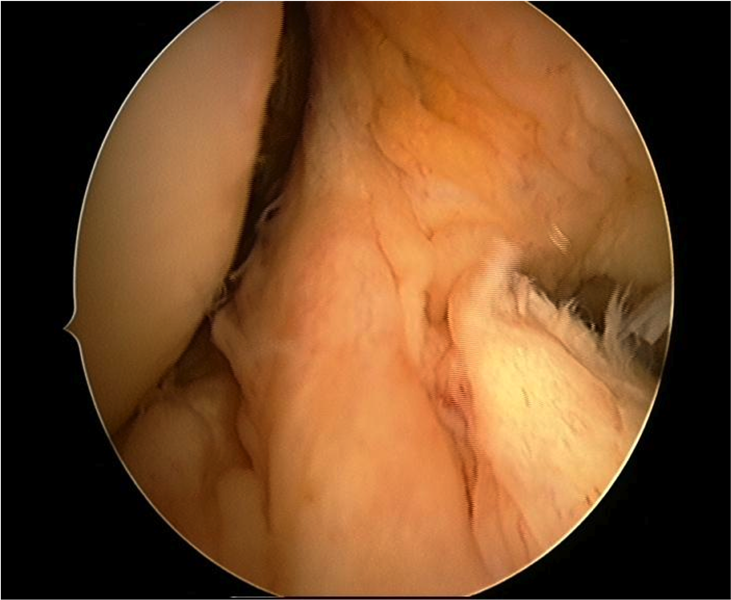

Rupture du ligament croisé antérieur (LCA)

Photos intra-articulaires d’une rupture et plastie du LCA

Rupture complète du ligament croisé antérieur